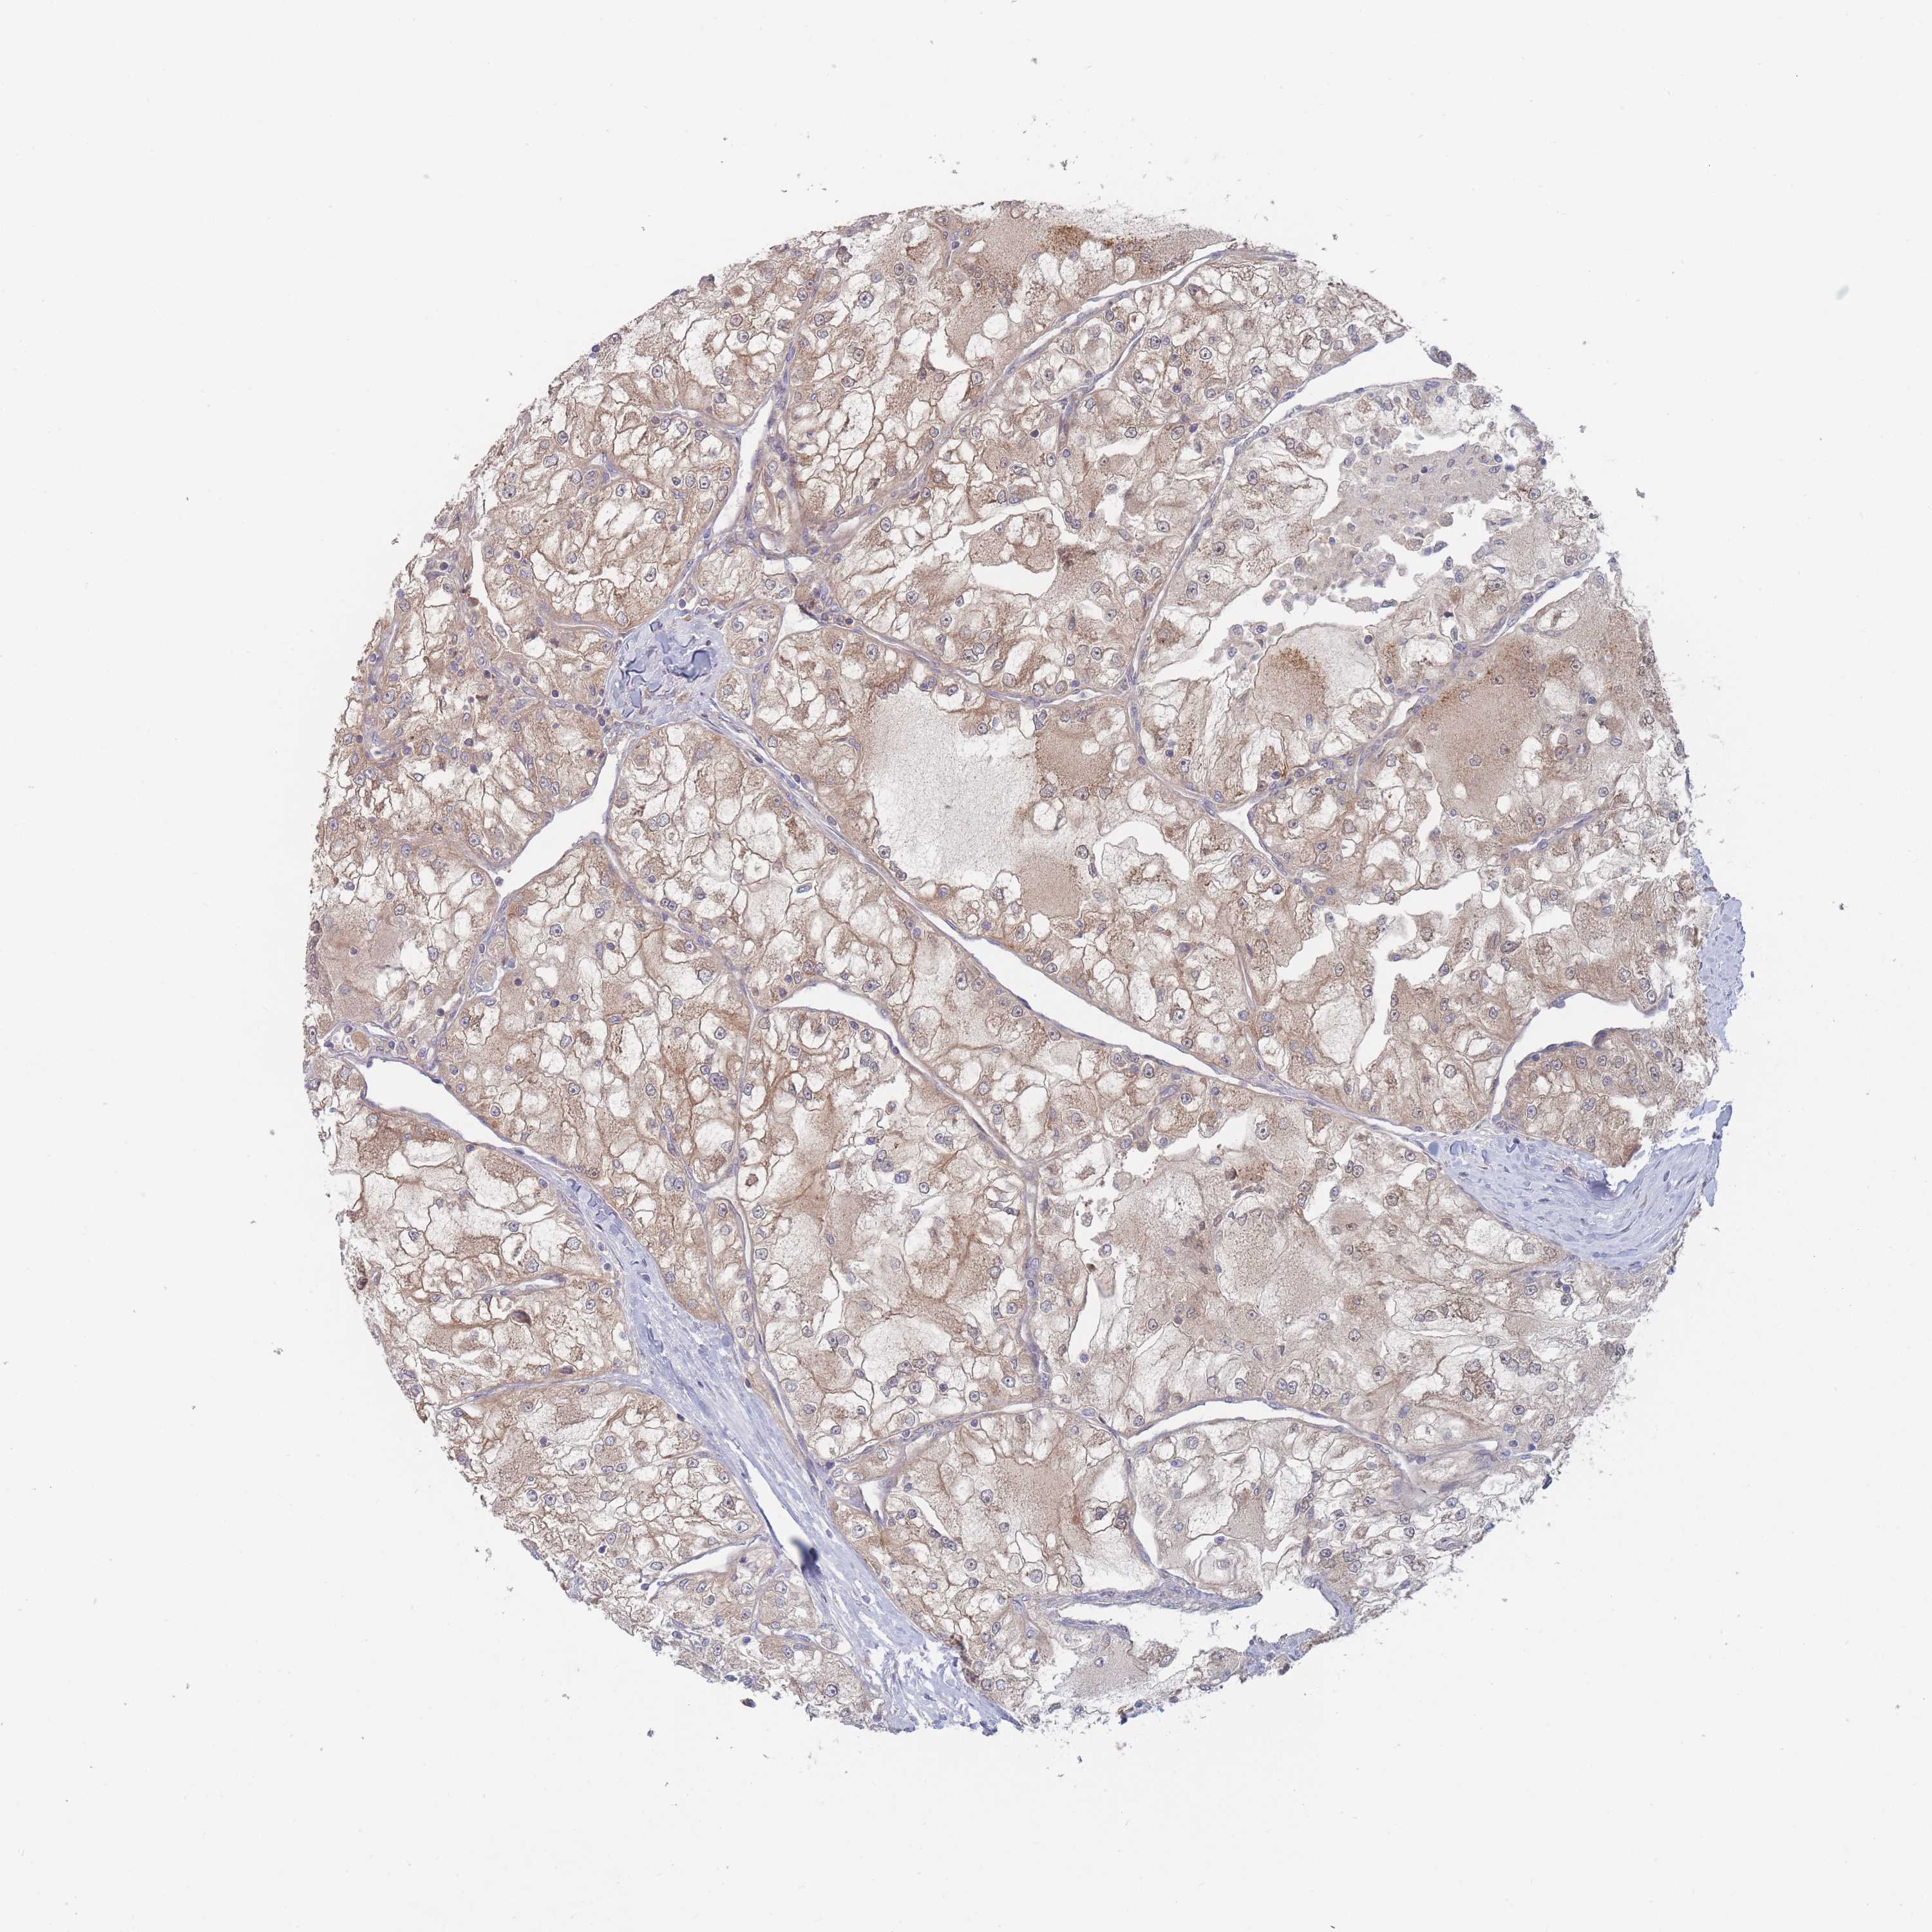

CANCER RENAL CANCER Show tissue menu

KICH TCGA KIRC TCGA KIRC VALIDATION KIRP TCGA PROTEIN RCC CPTAC PROTEIN EXPRESSION

KIDNEY RENAL CLEAR CELL CARCINOMA (VALIDATION) - Interactive survival scatter ploti

The Survival Scatter plot shows the clinical status (i.e. dead or alive) for all individuals in the patient cohort, based on the same data that underlies the corresponding Kaplan-Meier plots. Patients that are alive at last time for follow-up are shown in blue and patients who have died during the study are shown in red.

& Survival analysisi

Kaplan-Meier plots summarize results from analysis of correlation between mRNA expression level and patient survival. Patients were divided based on level of expression into one of the two groups "low" (under cut off) or "high" (over cut off). X-axis shows time for survival (years) and y-axis shows the probability of survival, where 1.0 corresponds to 100 percent.

EFCC1 is not prognostic in Kidney Renal Clear Cell Carcinoma (validation)

TCGA RNA samplesi

RNA-seq data is reported as average FPKM (number Fragments Per Kilobase of exon per Million reads), generated by the The Cancer Genome Atlas (TCGA) .

Normal distribution across the dataset is visualized with box plots, shown as median and 25th and 75th percentiles. Points are displayed as outliers if they are above or below 1.5 times the interquartile range. FPKM values of the individual samples are presented next to the box plot.

Average pTPM 2.0

Number of samples 100